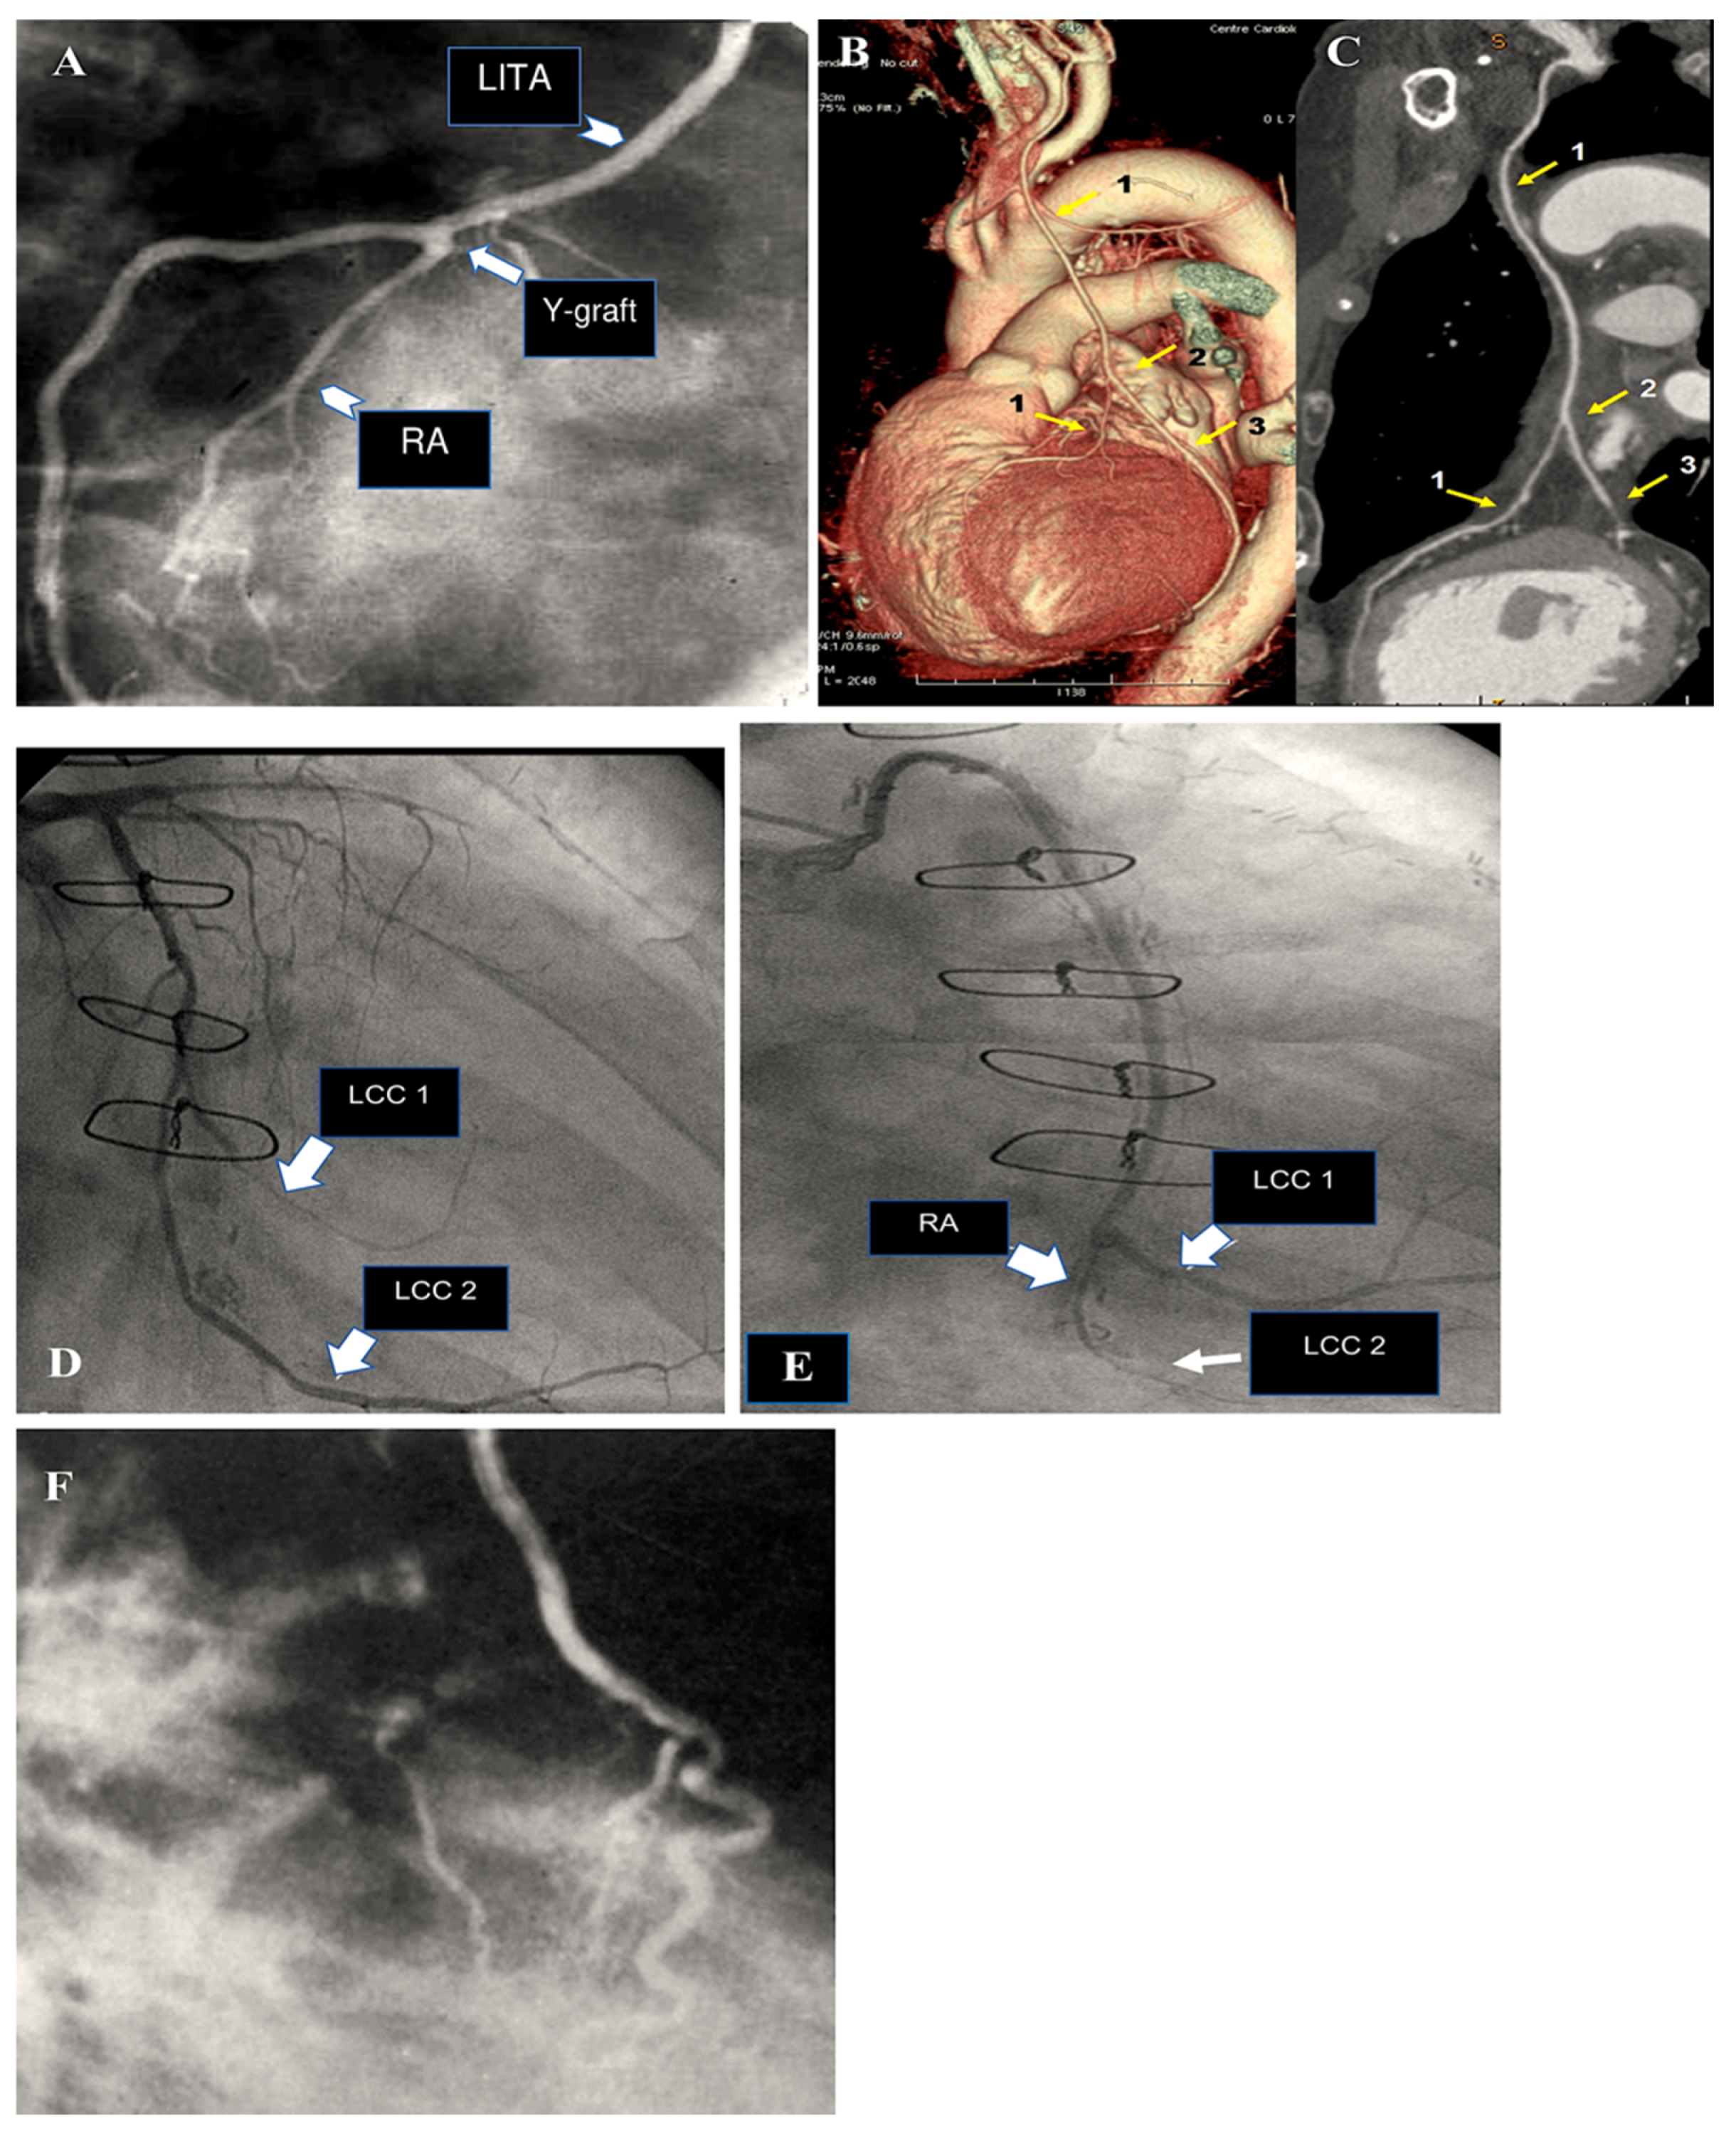

The most common type of angiographic failure observed in radial artery grafts is total obstruction, although a string-like appearance has also been documented. In rare instances, a localised stenosis of the radial artery graft has been identified [151]. Our own experience, spanning two decades, indicates that 6% of RA grafts exhibited stenosis on angiographic controls [151]. In some cases, stenosis was identified at either the proximal or distal anastomosis. In such instances, the potential culprits included a flawed surgical technique or intimal hyperplasia. In more frequent instances, stenosis affected the bodily region of the RA graft, thereby posing challenging pathophysiological concerns. It can often prove problematic to definitively exclude a spasm that is refractory to in situ vasodilators. If identified at an early stage following surgery, the stenosis can be treated with balloon dilation without the need for stenting [151]. If the stenosis is not identified in a timely manner, it is typically of an organic nature. It is possible that some narrowings existed prior to surgery involving the radial artery at the forearm. The development of RA stenosis may be attributable to the presence of an atheromatous plaque that had not been identified at the time of the initial surgical procedure. An additional possibility is that it is associated with fibrosis resulting from arterial trauma caused by inadequate harvesting techniques or prior intravascular procedures. It has been demonstrated that transradial angiography often results in intimal damage and/or medial dissection [152]. In certain instances, the stenosis of the radial artery was identified as a subsequent occurrence, as evidenced by instances where the graft was found to be intact in previous angiograms [151]. It seems plausible to suggest that these vessels may have been the focus of a preceding minor perivascular injury, which subsequently developed into a clinically significant flow-limiting stenosis. It can be reasonably deduced that the occurrence of RA graft stenosis may be prevented by the implementation of a systematic preoperative echo-doppler screening process, coupled with the deliberate preclusion of all calcified RAs and prior interventionally treated conduits. It is possible to safely treat RA graft stenoses by means of PCI and stenting, with the result being durable [151,153]. In regard to percutaneous interventions for venous graft disease, a significant challenge persists due to the high incidence of periprocedural morbidity associated with embolic complications from atherothrombotic detritus (Figure 6) [154].

Figure 6.

The illustration depicts the 20-year angiographic control of the radial artery as a secondary conduit on the right coronary artery (RCA), demonstrating the presence of a stenosis at the distal anastomosis. Panels (A–C) illustrate the balloon dilatation of the radial artery (RA) without the use of a stent.

Two distinct meta-analyses have corroborated this conclusion over the past two years, not only in larger cohorts of patients but also with longer-term follow-up. A single study encompassed 27 observational reports comprising a total of 79,000 patients, comprising approximately one-quarter of those with BITA. The findings indicated a statistically significant reduction in long-term mortality rates with BITA (p < 0.00001) [189]. An investigation conducted by Yi and Associates [190] included nine observational series of over 15,000 patients, representing approximately half of whom had BITA, with follow-up lasting a mean period of nine years. The analysis revealed a notable decline in fatality rates associated with BITA (HR: 0.79; 95% CI: 0.75 to 0.84). It is noteworthy that no study has documented any adverse impact of BITA on the fatality rate (Figure 7).

Figure 7.

CABG has been performed using best isolated technically appropriate anastomosis, either as an isolated termino-lateral graft with pediculate ITA or in a Y-shaped configuration with sequential BITA grafts. Controls have been achieved through the utilisation of computed tomography angiography. (A–F): The post-processing of computed tomography angiography of CABG was conducted using volume rendering and two-dimensional curved imaging with automatic tracking. (A–C): Illustrations of the utilisation of two-dimensional curved imaging in conjunction with automatic tracking in the context of CABG. (A): LITA has been anastomosed to the LAD. (B): LITA sequential grafting on LAD and the first diagonal branch. (C): RITA anastomosed on the first obtuse branch. (D–F): Volume rendering imaging of CABG. (D): 1. LITA, 2. LITA on the diagonal branch, and 3. LITA-LAD. (E,F): Illustrations of the grafting of the RITA on the CCA. The white arrow (1) indicates the course of the RITA between the aorta and the left atrium. (2) This image depicts distal grafting on the first obtuse branch. Abbreviations: CABG, coronary artery bypass grafting; CCA, circumflex coronary artery; LITA, left internal thoracic artery; LAA, left atrial appendance; LAD, left anterior descending artery; RCA, right coronary artery; RITA, right internal artery.